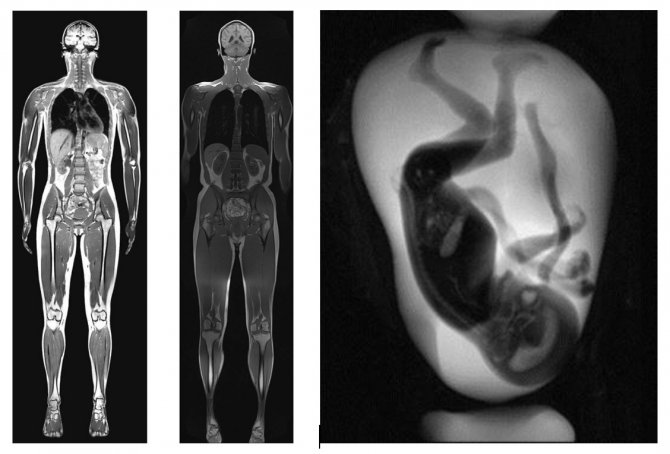

Günümüzde radyolojinin yalnızca tanı koyan değil, aynı zamanda tedavi sağlayan bir tıp branşı haline geldiğinden bahseden Prof. Dr. Nevzat Karabulut, "Başlangıçta sadece röntgen şeklinde başlayan Tıbbi Görüntüleme bugün radyasyon içeren (Röntgen, Mamografi, Floroskopi, Anjiyografi, Bigisayarlı Tomografi) ve radyasyon içermeyen (Ultrasonografi, Doppler, Manyetik rezonans görüntüleme) farklı enerjiler kullanarak vücudu ayrıntılı bir şekilde görüntüleyen bir branş haline gelmiştir. Günümüzde Radyoloji yalnızca tanı koyan değil, aynı zamanda tedavi sağlayan bir tıp branşı haline geldi. Tanısal Radyoloji hastalıklara erken ve doğru tanı koyarak tedaviyi şekillendirir ve tedaviye yanıtı değerlendirir. Anne karnındaki bebeğin değerlendirmesinden korona virüs, kemik kırığından bağ yırtığına, safra taşından böbrek taşına, doğumsal anomalilerden kalp hastalıklarına ve kanserden inmeye kadar pek çok hastalık radyolojik tetkiklerle erken ve doğru şekilde teşhis edilebilmektedir. Girişimsel Radyoloji ise görüntüleme yöntemleri rehberliğinde iğne deliğinden tedavi sağlayarak ve birçok hastayı ameliyattan kurtaran bir alandır. Apse ve kist tedavisinden tıkalı damarların açılmasına ve kanserli dokunun tedavisine kadar pek çok sorun genel anestezi ve ameliyata gerek kalmadan küçük bir iğne deliğinden girilerek tedavi edilebilmektedir. Yani Radyoloji Tıbbın gören gözleri ve bel kemiği iken, radyolog ise tanı koyan, tedaviyi şekillendiren ve şifa dağıtan görünmeyen yüzleridir" dedi.